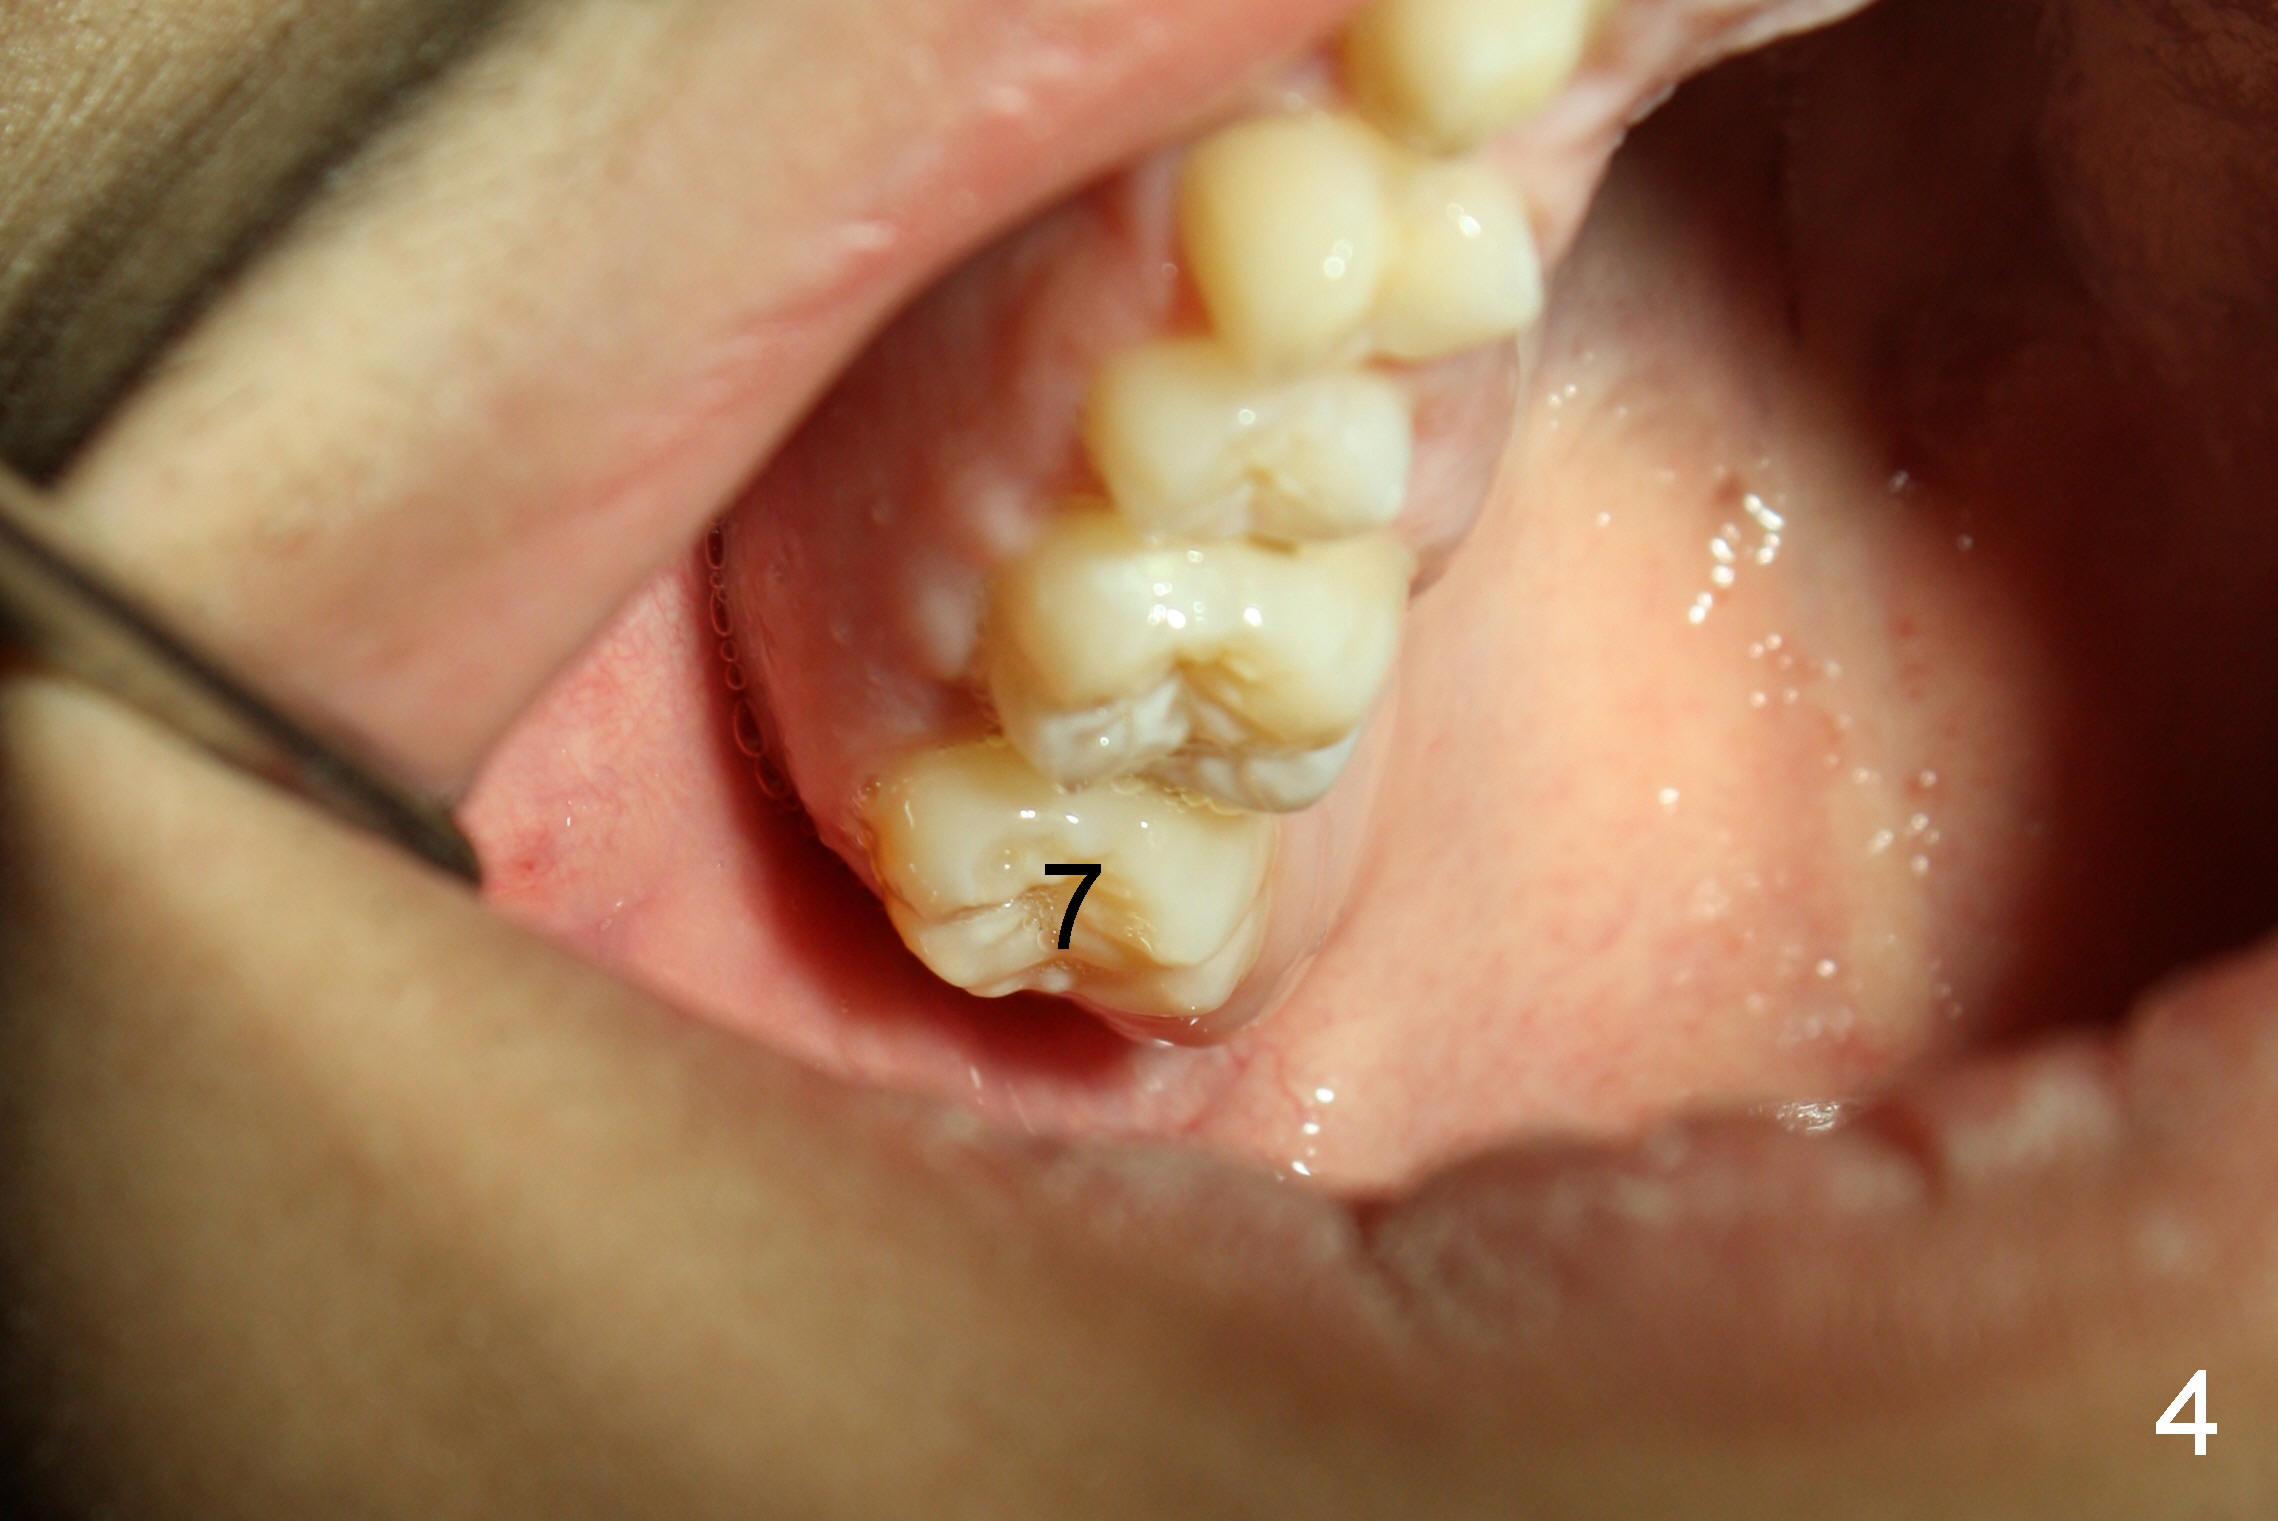

打完下颌神经麻药,乘麻药还没有奏效,拍摄图二至图五,图二,图三显示前牙第一类咬合,而后牙第三类,上颌第二磨牙(7)咬在下颌牙龈(*,仿佛形成白斑(leukoplakia))。图四,图五显示上颌第二磨牙向下伸长。那时我还不具有力挽狂澜能力。那么这四个智齿该拔吗?